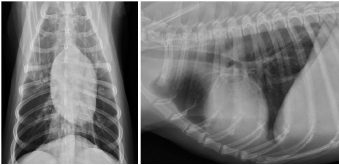

AbstractBackground: There are few detailed reports on implant-associated sarcoma in dogs; however, loose implants, metal type, and infection have not been shown as specific risk factors for this condition. Case Description: A 14-year-old spayed female Labrador retriever was referred to our hospital with a main complaint of chronic right hind lameness after previous tibial fracture repair. On radiographs, rupture of the bone plate and screws with swelling of the surrounding soft tissue was observed, and osteosarcoma (OSA) was diagnosed after histopathological examinations. During amputation surgery, a plastic band was found associated with the implant. Conclusion: Veterinary surgeons should be aware of implant-associated OSA and refrain from using non-medical materials in the implants. Furthermore, they should recommend the removal of orthopedic implants after fracture repair. Keywords: Dogs, Fracture, Implant, Osteosarcoma, Repair. IntroductionOsteosarcoma (OSA) is a highly aggressive mesenchymal tumor that comprises at least 85% of canine bone tumors (Egenvall et al., 2007) and tends to occur in larger individuals, and the most common site in dogs is in the appendicular skeleton near metaphyses (Morello et al., 2011). Several studies have suggested that OSAs result from abnormalities in osteoblast differentiation, as mesenchymal stem cells differentiate through osteoprogenitor and osteoblast phases before becoming mature osteocytes (Tang et al., 2008). Osteoblastic features are common in OSA, suggesting that early disruption of osteogenic differentiation may occur during sarcoma development (Tang et al., 2008). Furthermore, this process is sometimes initiated by the presence of orthopedic implants (Murphy et al., 1997; Rose et al., 2005). Loose implants, metal type, and infection have not been shown to be specific risk factors of implant-associated sarcoma (Sinibaldi et al., 1976; Kenecht et al., 1978; MacDonald et al., 2012). There have been a few reports on implant-associated sarcoma in dogs, albeit with minimal information (Burton et al., 2015; Arthur et al., 2016). Our case describes canine implant-associated OSA at the site of a previous fracture, repaired with bone plate and screws and an unknown plastic band. Case DetailsA 14-year-old spayed female Labrador retriever weighing 21.3 kg was referred to our hospital with a main complaint of chronic right-hind lameness. This patient had undergone surgery for right tibial fracture repair with implantation of bone plate and screws at a referral hospital 12 years ago. The patient showed no appetite, was not drinking, and was lethargic, with a body condition score of 1/5. The patient was unable to stand up on her own, her right hind limb was mostly weak, and she was unable to move independently using her left side. The patient’s state of consciousness was normal. On physical examination, her vital signs were normal (temperature: 38.1°C, pulse 104 beats/minutes with no heart murmur, respiratory rate with normal lung sounds: 32 beats/minutes). The mucous membrane showed a pale color because of severe anemia (packed cell volume 20.4%). In addition, the capillary refill time was delayed by <3 seconds, suggesting severe dehydration. The patient showed swelling and was warm to the touch from the right tibia to the femur, with a swollen right popliteal lymph node, which presented with a ruptured mass lesion approximately 7 × 10 cm in size. The thoracic radiograph was normal (Fig. 1). However, the right hind limb radiograph showed an osteolytic lesion accompanying the ruptured implant and loosening of the plate and screws, with surrounding soft tissue swelling (Fig. 2). Fine needle aspiration from this site suggested OSA (data not shown). Although we could not perform angiographic computed tomography because of the owner’s dissent, we performed amputation from the hip joint on the same day. Gross morphology showed severe inflammation surrounding soft tissues, the rupture of the stainless-steel bone plate, and we noted a non-medical band at the right tibia (Fig. 3). The patient was formally diagnosed with OSA after histopathological examinations (Fig. 4). After 24 hours hospitalization, we administered ampicillin potassium (20 mg/kg, BID) intravenously and prednisolone (0.5 mg/kg, SID) subcutaneously for postoperative care. Also, 24 hours continuous rate infusion of fentanyl (5 μg/kg/minutes) in lactated Ringer’s solution was used for analgesia. The patient was discharged to the owner the day after surgery for home care. The owner refused postoperative radiation therapy and chemotherapy. Unfortunately, this patient died 1 month after amputation.

Fig. 1. Thoracic radiographs.

No metastasis was observed. Fig. 2. Limb radiographs. The right tibia showed an osteolytic lesion with rupture of orthopedic plate, loosening of screws, and also soft tissue swelling. DiscussionOrthopedic implants are commonly used in small animal patients, including dogs, and hence an awareness of potentially serious complications is important. In a study of more than 19,000 open fracture restoration cases in canines occurring between 1970 and 2000, only 15 cases of OSA had occurred at the site of fracture restoration. In other words, the incidence of OSA at a fracture site was less than 0.08% (Arthur et al., 2016). Although long-term inflammation is recognized as a contributing factor to creating an environment promoting tumorigenesis, this relationship has not been demonstrated in reports of implant-associated malignancy. While the effects of implant composition and wear have received great attention, the role of chronic inflammation in the development of sarcoma remains a point of interest (Visuri et al., 2006). Many initiating factors have been hypothesized to play a role in the development of implant-associated sarcoma. Researchers have shown that many implant materials, including commonly used stainless steel and titanium, have potentially carcinogenic properties (Kirkpatrick et al., 2000). Consequently, some surgeons suggest the removal of orthopedic implants after fracture repair. In our case, non-medical bands had been used to surround the bone plate, probably leading to severe inflammation and resulting in the occurrence of OSA at the fracture site. In veterinary medicine, there are few reports about canine implant-associated neoplasia (Burton et al., 2015; Arthur et al., 2016). In a retrospective study of 16 cases of canine implant-associated tumors, it was determined that tumors developed an average of 5.5 years after implant placement. In addition, the hind limbs [tibia (8/16) and femur (5/16)] were favored; 15 of the 16 cases developed in the bone trunk and 13 were OSAs (Burton et al., 2015). Our case showed the same features as those documented in the previous report (Burton et al., 2015).